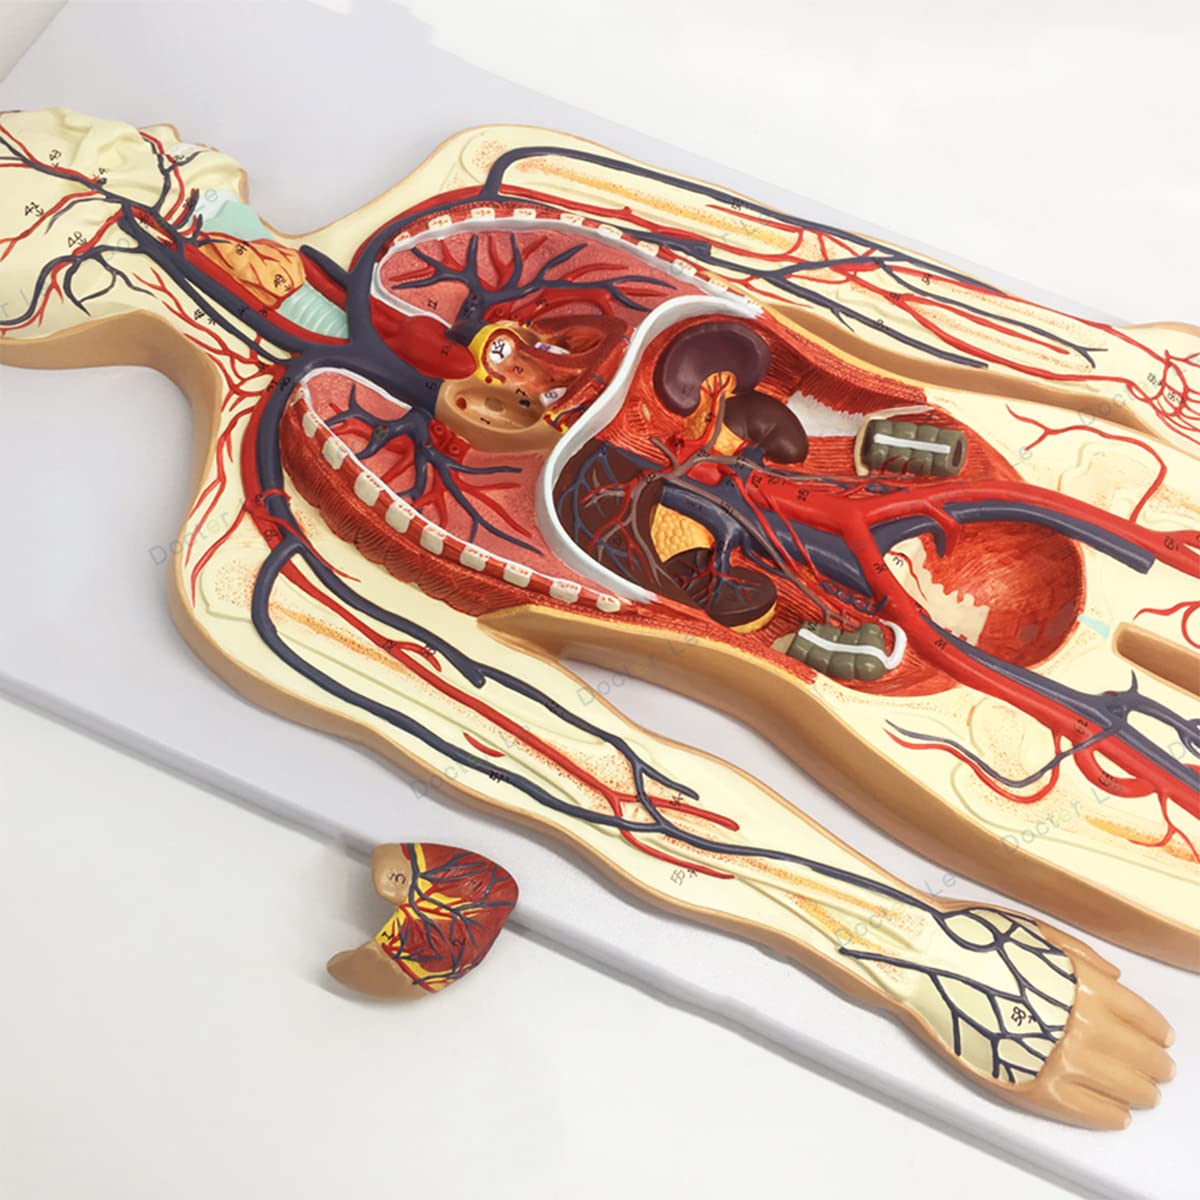

- Features: This model shows the structure of blood circulation in various parts of the human body. The circulatory system is the channel through which blood flows in the body and is divided into two parts: the cardiovascular system and the lymphatic system. Blood circulation route: superior and inferior vena cava → right atrium → right ventricle → pulmonary artery - → alveolar surrounding → pulmonary veins - >> left atrium → left ventricle → aorta - → systemic tissues (except lung). Product Size: Using this model helps to understand the composition and structure of human blood circulation. The size of the model is 1/2 the size of the human blood circulatory system. Product size: 90*30 cm/35.4*11.8 inches. High Quality: High-quality prototypes, sturdy hand-made, not fragile, made of high-quality environmentally friendly PVC, fine workmanship, creating good objects with clear shapes and rich details. Meticulous workmanship: The model has meticulous workmanship, realistic details, clear texture, easy to use and easy to observe. This product comes with a base, which is convenient for learning and teaching. Good Teaching Aids: This collection is designed for anatomy professionals and students. We are sure you will love these models. Can also be given as a gift to educators or doctors, excellent educational tool for students/teachers/professionals.

Product Specifications:Product name: Human Blood Circulatory System Model Product Type: Medical Teaching Model Product material: PVCProduct use: medicine, school, hospital, medical giftPackage list:Human Blood Circulatory System Model *1Notice:The monitor calibration is different, and the color of the object shown in the photo may be slightly different from the actual product. Please refer to the actual product.